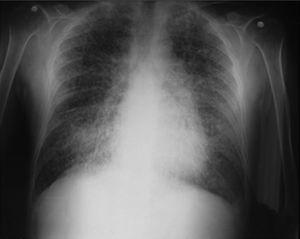

Para la realización del diagnóstico, se puede contar con diferentes medios, el más sencillo es el estudio directo de esputo en busca específica de microlitos, aunque su rendimiento diagnóstico es limitado1,3figuras 1–4.

Radiografía tórax con partículas de arena en ambos campos pulmonares.

Figura 1.

(0,09MB).

Dentro de los exámenes diagnósticos se debe realizar, en primer lugar, una radiografía de tórax, que usualmente muestra calcificaciones micronodulares, bilaterales, opacidades reticulares lineales y uniformidad de tamaño de los microlitos distribuidos a lo largo de todo el árbol bronquial. Los anteriores hallazgos se han descrito como «tormenta de arena» (del inglés sandstorm)44 o «tormenta de nieve» (del inglés snowstorm)45, que predominan en las áreas basales y mediales del pulmón, con obliteración de los bordes cardiacos y diafragmáticos35.

Se observan depósitos en las superficies subpleurales, resultando en una opacidad lineal, que demarca las divisiones pulmonares y mediastinales46, conocida como línea negra pleural (del inglés black pleural line), la cual fue descrita por Felson, considerada como una ilusión visual secundaria a un área radiolucente que se da entre el parénquima pleural y las costillas45,47–50. Otros hallazgos típicos son pequeñas bulas apicales e imagen en panal de abejas, sin mención de compromiso de nódulos linfáticos51.

Se esclareció este diagnóstico, dado que el hermano del paciente presentaba una entidad, que en principio el servicio desconocía pero que se había establecido varios años atrás como MAP, después de un chequeo médico de rutina. Se intentó tener acceso a los datos clínicos del hermano, pero no fue posible, se rescató una radiografía suministrada por el mismo familiar, de cuando se hizo el diagnóstico.

Una vez conocida esta información se citó a los otros hermanos, pero solo se tuvo acceso a la radiografía de la hermana mayor, que no mostraba anormalidad alguna.